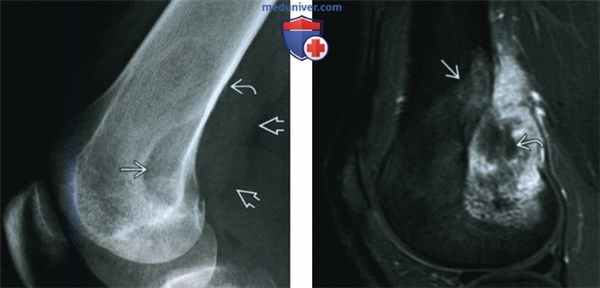

(Слева) Рентгенография в боковой проекции: агрессивный литический очаг у мужчины 22 лет. Очаг расположен эксцентрично, имеются признаки периостальной реакции и прорыва кортикального слоя с мягкотканным компонентом. Агрессивные, но неспецифические признаки роста обусловливают широкий дифференциально-диагностический поиск.

(Справа) МРТ, сагиттальная проекция, режим Т1 с подавлением сигнала от жира, с контрастным усилением: патологический очаг с сопутствующей обширной зоной отека костного мозга. Мягкотканный компонент активно накапливает контрастное вещество и имеет центральную зону некроза. При биопсии диагностирована фибросаркома. Лучевые признаки указывают на агрессивность процесса, но не являются специфичными.

2. Рентгенография при фибросаркоме:

• Агрессивный, деструктивный очаг:

о Проникающий характер, широкая переходная зона

• Литический очаг, может содержать костные секвестры

• Имеет центральное или эксцентричное расположение

• Прорыв кортикального слоя с мягкотканным компонентом

3. МРТ при фибросаркоме:

• Неспецифический агрессивный очаг:

о В режиме Т1 очаг характеризуется изоинтенсивностью по отношению к скелетной мышце

о Последовательности, чувствительные к жидкости: неоднородная гиперинтенсивность

о Активное накопление контрастного вещества